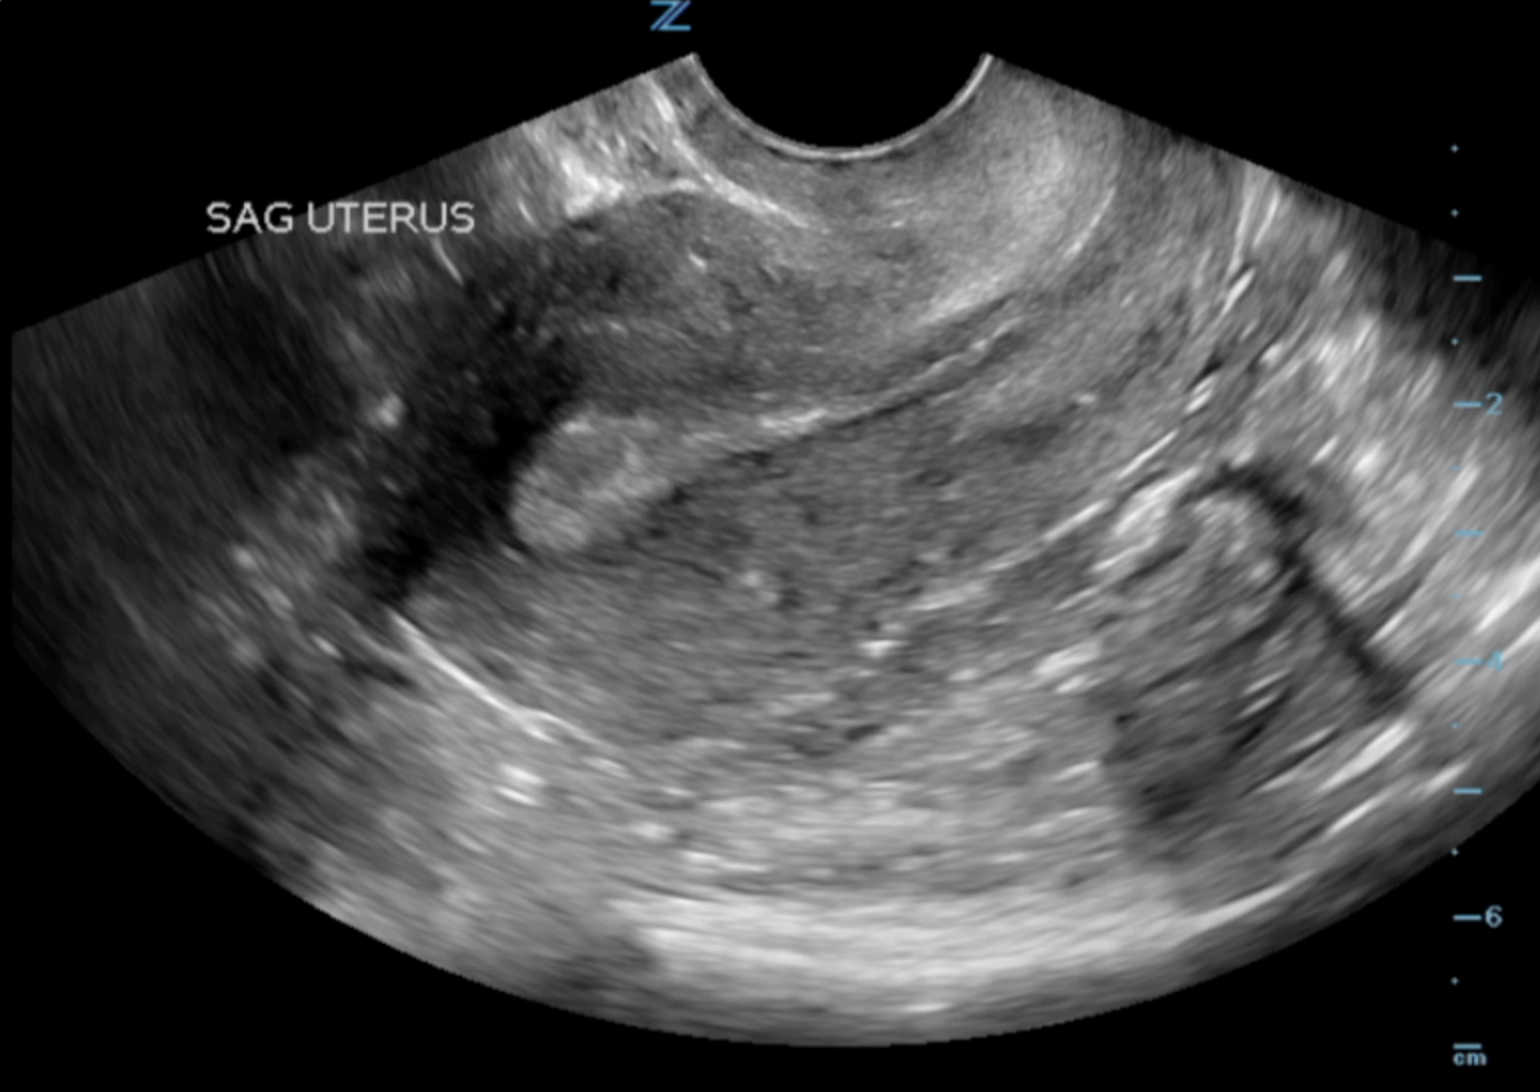

Sonographic Technique – Transvaginal

- Patient should be supine in lithotomy position.

- Use a 5-9 MHz endocavitary or transvaginal probe with a water based/non-irritating lubricant and probe cover.

- Insert or have the patient insert the probe into the vagina with probe indicator towards to ceiling. This is the sagittal/longitudinal plane. (Illustrations 7 and 8)

- Fan right to left to view the entire uterus.

- Illustration 7. Graphic of sagittal or longitudinal transvaginal approach with relevant anatomy. Probe indicator towards the ceiling. Source: WikiCommons (https://commons.wikimedia.org/wiki/File:Vaginal_Ultrasound.png)

- Illustration 8. Image of transvaginal sagittal/longitudinal view. Notice hyperechoic (bright) endometrial stripe.